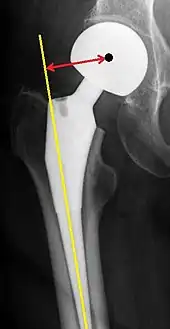

Hemiarthroplasty

Femoral (neck) offset is defined as the perpendicular distance between the intramedullary or longitudinal axis of the femur and the center of rotation of the native or prosthetic femoral head. An offset of less than 33 mm is associated with hip dislocation.[98][99]

Hemiarthroplasty is a surgical procedure that replaces one half of the joint with an artificial surface and leaves the other part unchanged. This class of procedure is most commonly performed on the hip after an intracapsular fracture of the femur neck (hip fracture). The procedure is performed by removing the head of the femur and replacing it with a metal or composite prosthesis. The most commonly used prosthesis designs are the Austin Moore and Thompson prostheses. A composite of metal and high-density polyethylene that forms two interphases (bipolar prosthesis) can be used. The monopolar prosthesis has not been shown to offer any advantage over bipolar designs. The procedure is recommended only for elderly/frail patients, due to their lower life expectancy and activity level. This is because over time the prosthesis tends to loosen or to erode the acetabulum.[100] Independently mobile older adults with hip fractures may benefit from a total hip replacement instead of hemiarthroplasty.[101]